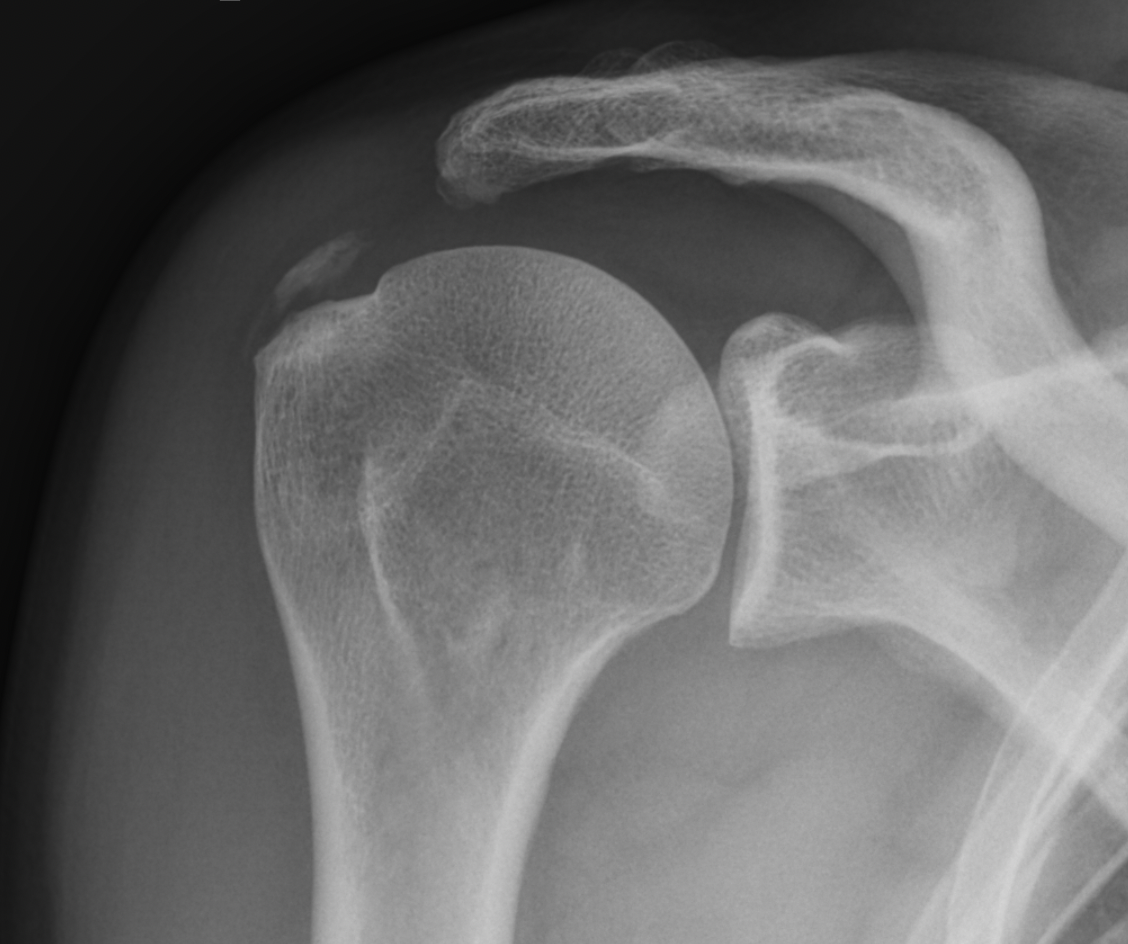

- Osteosynthese